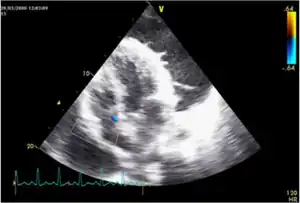

| Rounded, bulging mass in the superior cardiac border and adjacent lung nodule arrow on chest X-ray. | |